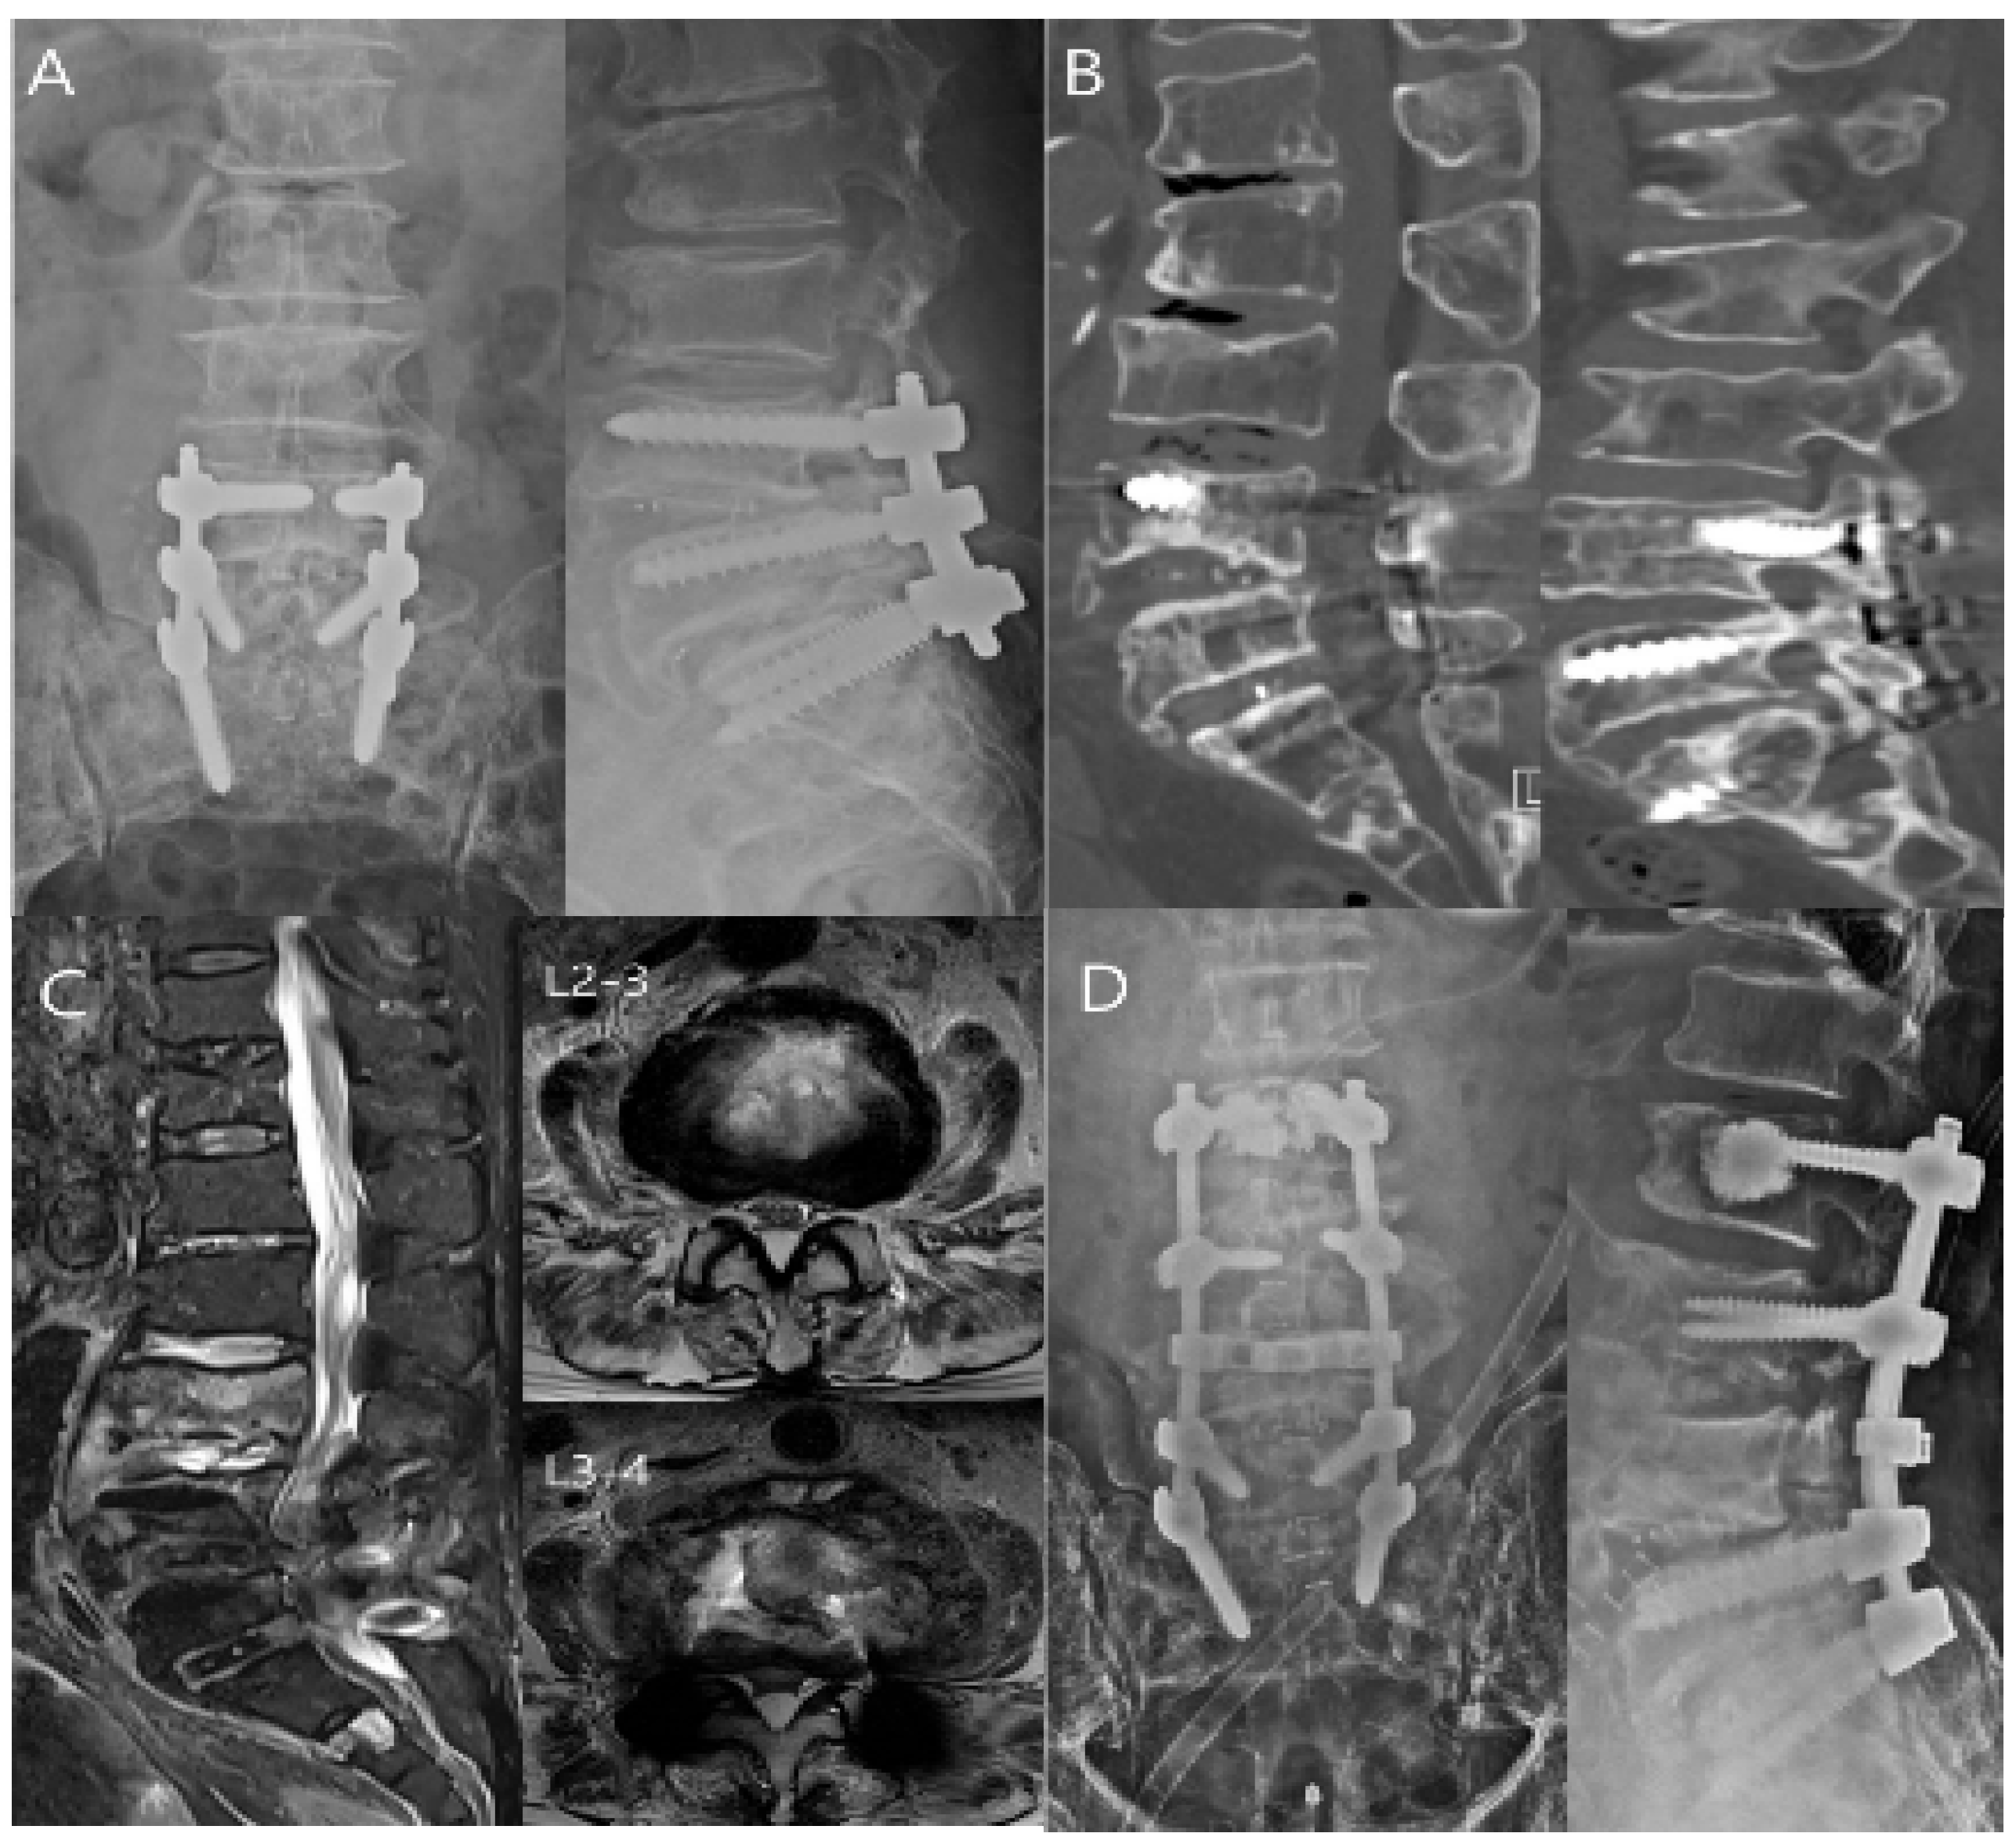

- Stüer, C.; Stoffel, M.; Hecker, J.; Ringel, F.; Meyer, B. A staged treatment algorithm for spinal infections. J. Neurol. Surg. A Cent. Eur. Neurosurg. 2013, 74, 87–95. [Google Scholar] [CrossRef]

- Hadjipavlou, A.G.; Mader, J.T.; Necessary, J.T.; Muffoletto, A.J. Hematogenous pyogenic spinal infections and their surgical management. Spine 2000, 25, 1668–1679. [Google Scholar] [CrossRef]

- Dimar, J.R.; Carreon, L.Y.; Glassman, S.D.; Campbell, M.J.; Hartman, M.J.; Johnson, J.R. Treatment of pyogenic vertebral osteomyelitis with anterior debridement and fusion followed by delayed posterior spinal fusion. Spine 2004, 29, 326–332. [Google Scholar] [CrossRef] [PubMed]

- Lu, D.C.; Wang, V.; Chou, D. The use of allograft or autograft and expandable titanium cages for the treatment of vertebral osteomyelitis. Neurosurgery 2009, 64, 122–129. [Google Scholar] [CrossRef] [PubMed]

- Lee, B.H.; Lee, H.-M.; Kim, T.-H.; Kim, H.-S.; Moon, E.-S.; Park, J.-O.; Chong, H.-S.; Moon, S.-H. Transpedicular Curettage and Drainage of Infective Lumbar Spondylodiscitis: Technique and Clinical Results. Clin. Orthop. Surg. 2012, 4, 200–208. [Google Scholar] [CrossRef]